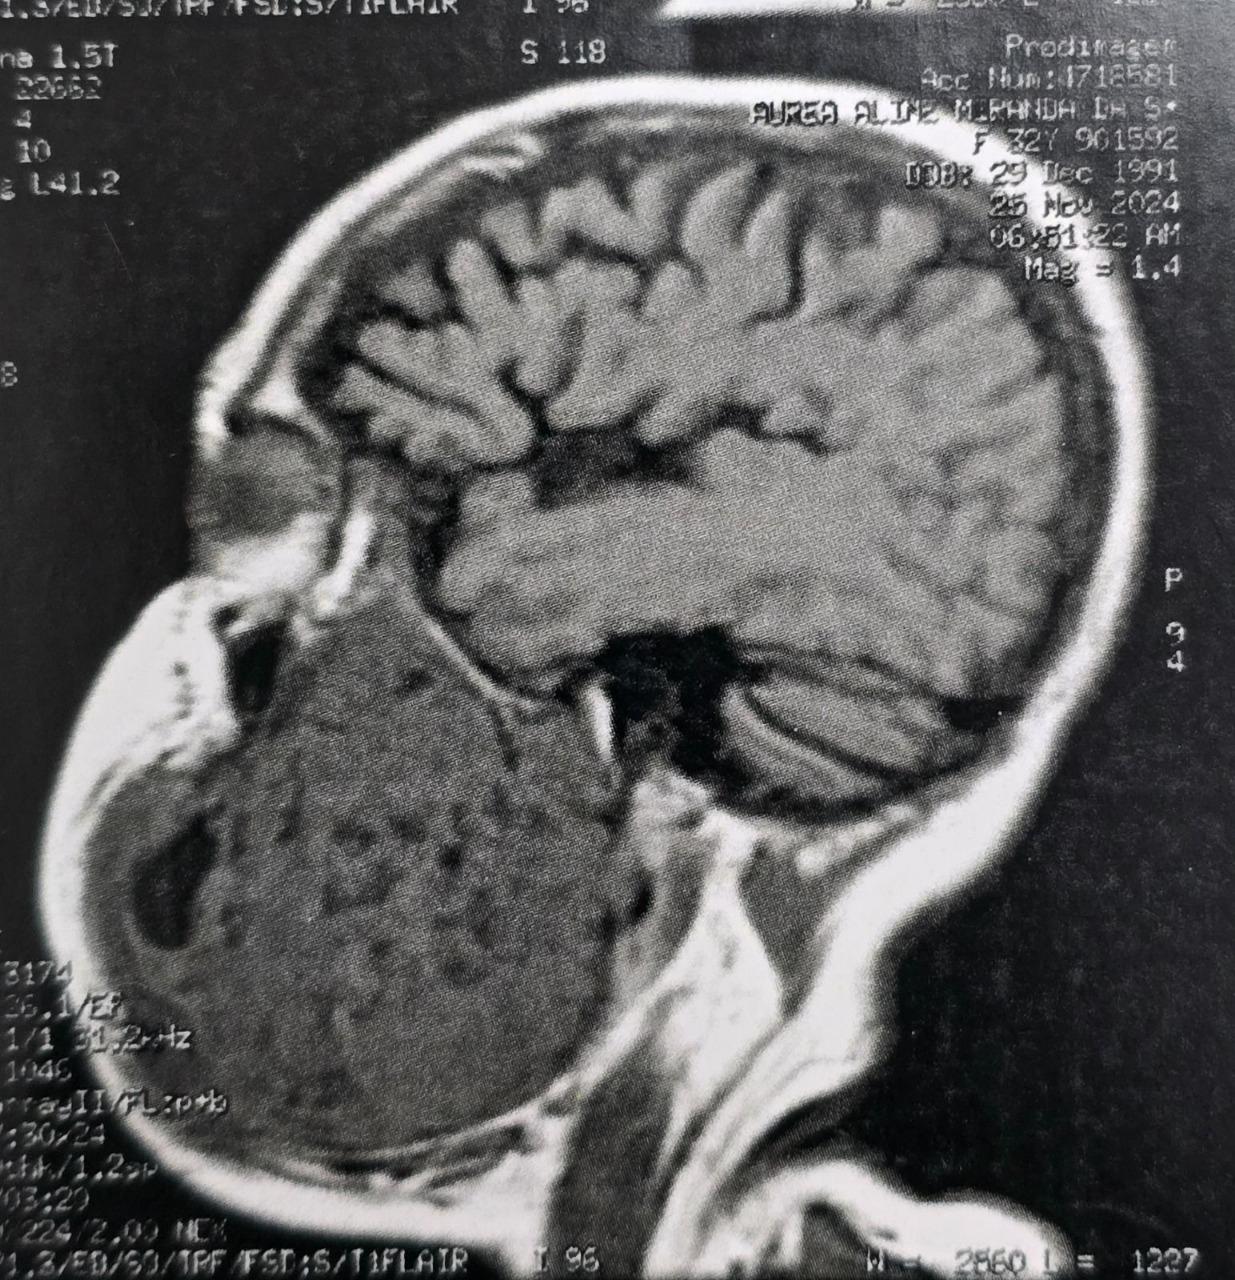

O tumor, diagnosticado como um ameloblastoma agressivo, comprometia aproximadamente 50% da mandíbula esquerda da paciente, provocando deformidade facial severa, além de grandes dificuldades para se alimentar e se comunicar. Natural do estado do Pará, a paciente convivia com o problema há oito anos e chegou a perder 30 quilos nos últimos meses.

A cirurgia mobilizou médicos altamente especializados das áreas de bucomaxilofacial, microcirurgia de cabeça e pescoço, além de cirurgia plástica. De acordo com o cirurgião bucomaxilofacial Flávio Fayad, o planejamento do procedimento envolveu exames detalhados e discussões clínicas ao longo dos últimos meses. “Foi uma cirurgia complexa, mas conduzida com precisão. Realizamos a ressecção completa do tumor, instalamos uma placa de reconstrução mandibular e, por fim, fizemos um enxerto de fíbula vascularizada, técnica que utiliza parte do osso da perna para reconstruir a mandíbula”, explicou.